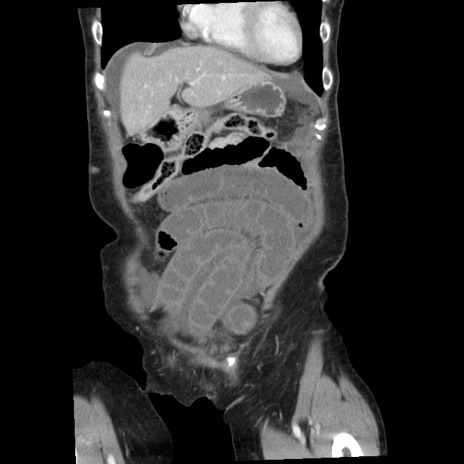

矢状断像